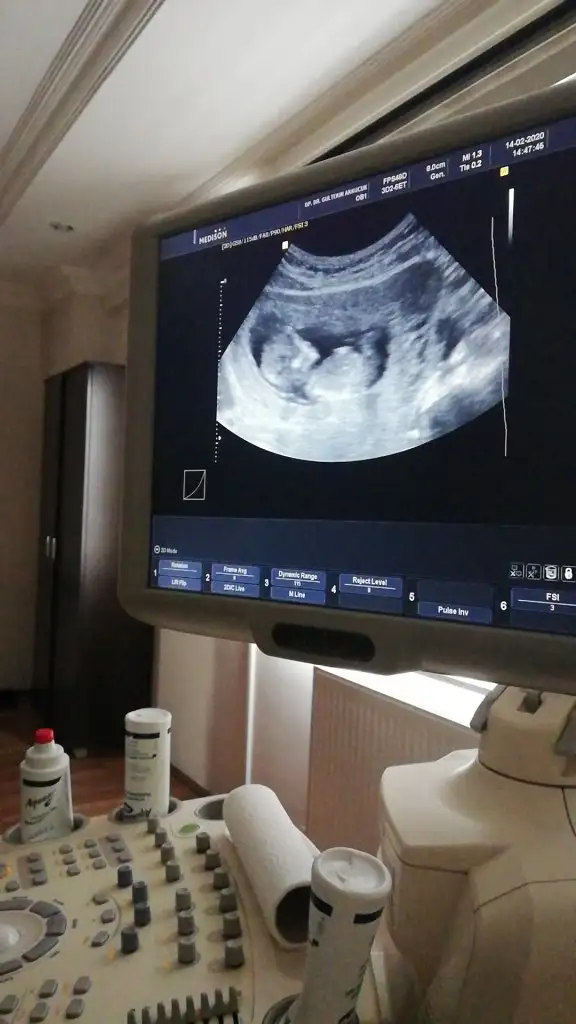

dr soylemeden siz gorun genital nub teorisi ( bebegin cinsiyeti)

Merhabalar Tahmin yorumlarınızı heyecanla takip ediyorum. Bende sabırla 12. haftamızın dolmasını bekledim. Bir yorumda benim için yaparmısınız Buğün 12+1 olduk.